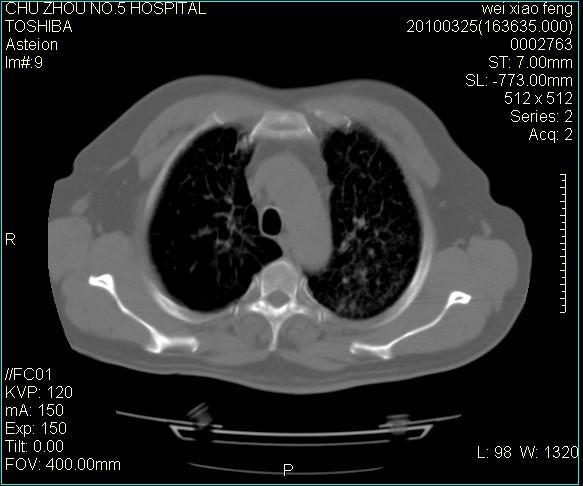

男,60岁,反复咳、痰、喘3月,加重3天。

双肺间质性改变。

考虑双肺血型潘散肺结核/

间质性肺炎伴间质纤维化!不排除伴有职业病!

急性血型潘散肺结核。

双肺间质纤维化,双肺血型潘散肺结核。

考虑尘肺

考虑间质性肺炎伴间质纤维化。

间质性肺炎